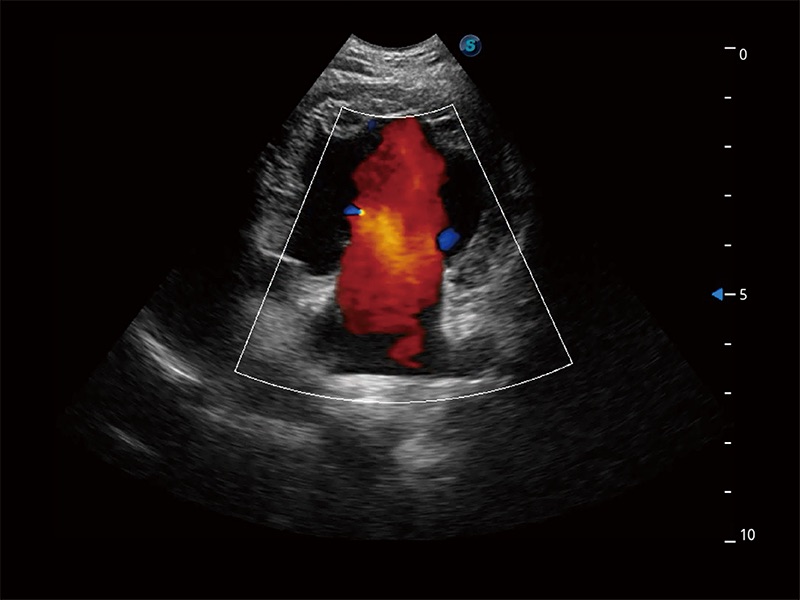

ProPet 80 配备了丰富的心脏探头群、先进的成像技术和专业的心脏测量工具,可帮助动物医生为不同体型和生理结构的动物提供心脏和心肌功能的全面评估。

能够基于左心室壁追踪和辛普森法,自动计算射血分数,支持多个可移动点描迹,与手动测量相比,极大节省了动物医生的时间和精力。